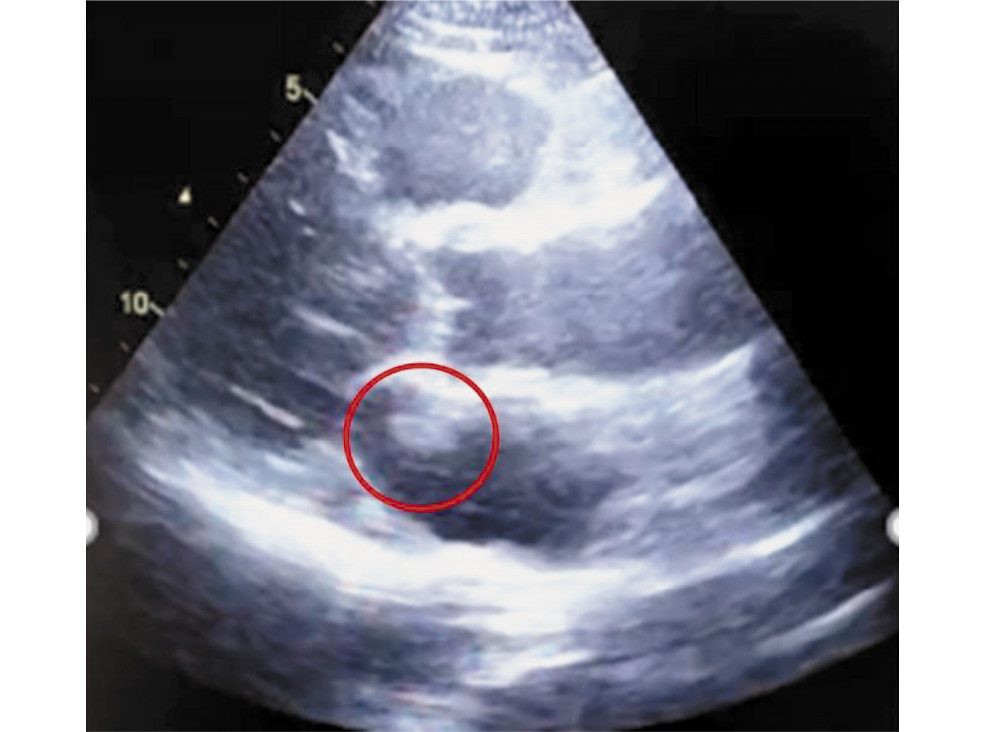

Для окончательной верификации образования в ЛП (тромб / миксома), определения его размеров и выбора дальнейшей тактики лечения была проведена МРТ сердца с гадолинием. По результатам исследования: МР-признаки мелкого образования ЛП, по МР-характеристикам более соответствующего миксоме — мелкое флотирующее образование неправильной формы ориентировочного размера 10×12 мм, фиксированное на уровне средней / нижней трети МПП и направленное в полость ЛП (рис. 2). Образование состоит из «ножки» размером 5×5 мм с изоинтенсивным МР-сигналом на DIR-ИП (импульсная последовательность в режиме Double Inversion Recovery) и гиперинтенсивным — на TIR-ИП (Tau Inversion Recovery), T2 FS-ИП (Fat Suppression), и более «рыхлой» части, слабо дифференцирующейся на киноизображениях и имеющей слабогиперинтенсивный МР-сигнал на TIR-ИП (на рис. 2 — МР-картина постишемического практически трансмурального рубца — нежизнеспособный миокард) в 7-м сегменте передней стенки ЛЖ, наблюдается концентрическая гипертрофия миокарда ЛЖ.

Рис. 2. Четырёхкамерная проекция. Флотирующее образование в нижней трети межпредсердной перегородки (красным цветом обозначена миксома). / Fig. 2. Four-chamber projection. Floating formation in the lower third of the interatrial septum (myxoma is marked in red).